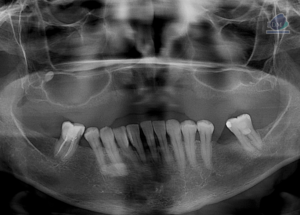

Paciente femenino de 48 años de edad, es referido al Instituto de Diagnóstico Maxilofacial – IDM para evaluación general.En la radiografía panorámica (Figura 1), se